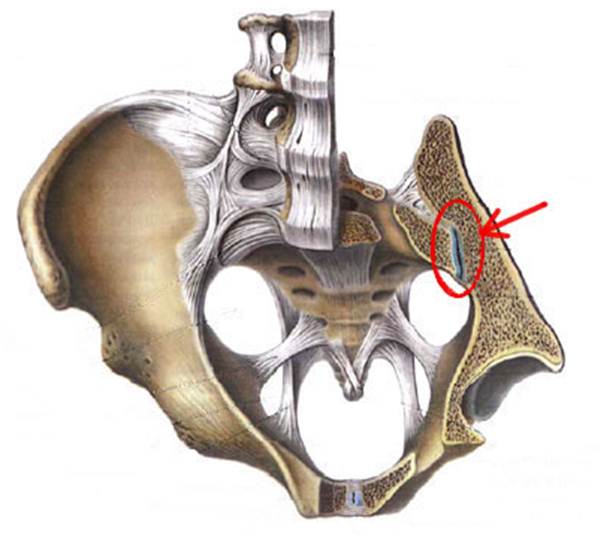

S: Стрелка указывает на art. sacroiliaca (латинский язык).

S: Стрелка указывает на lig. Sacroiliaca posteriora

S: Стрелка указывает на facies auricularis

S: Стрелка указывает на facies sacropelvica